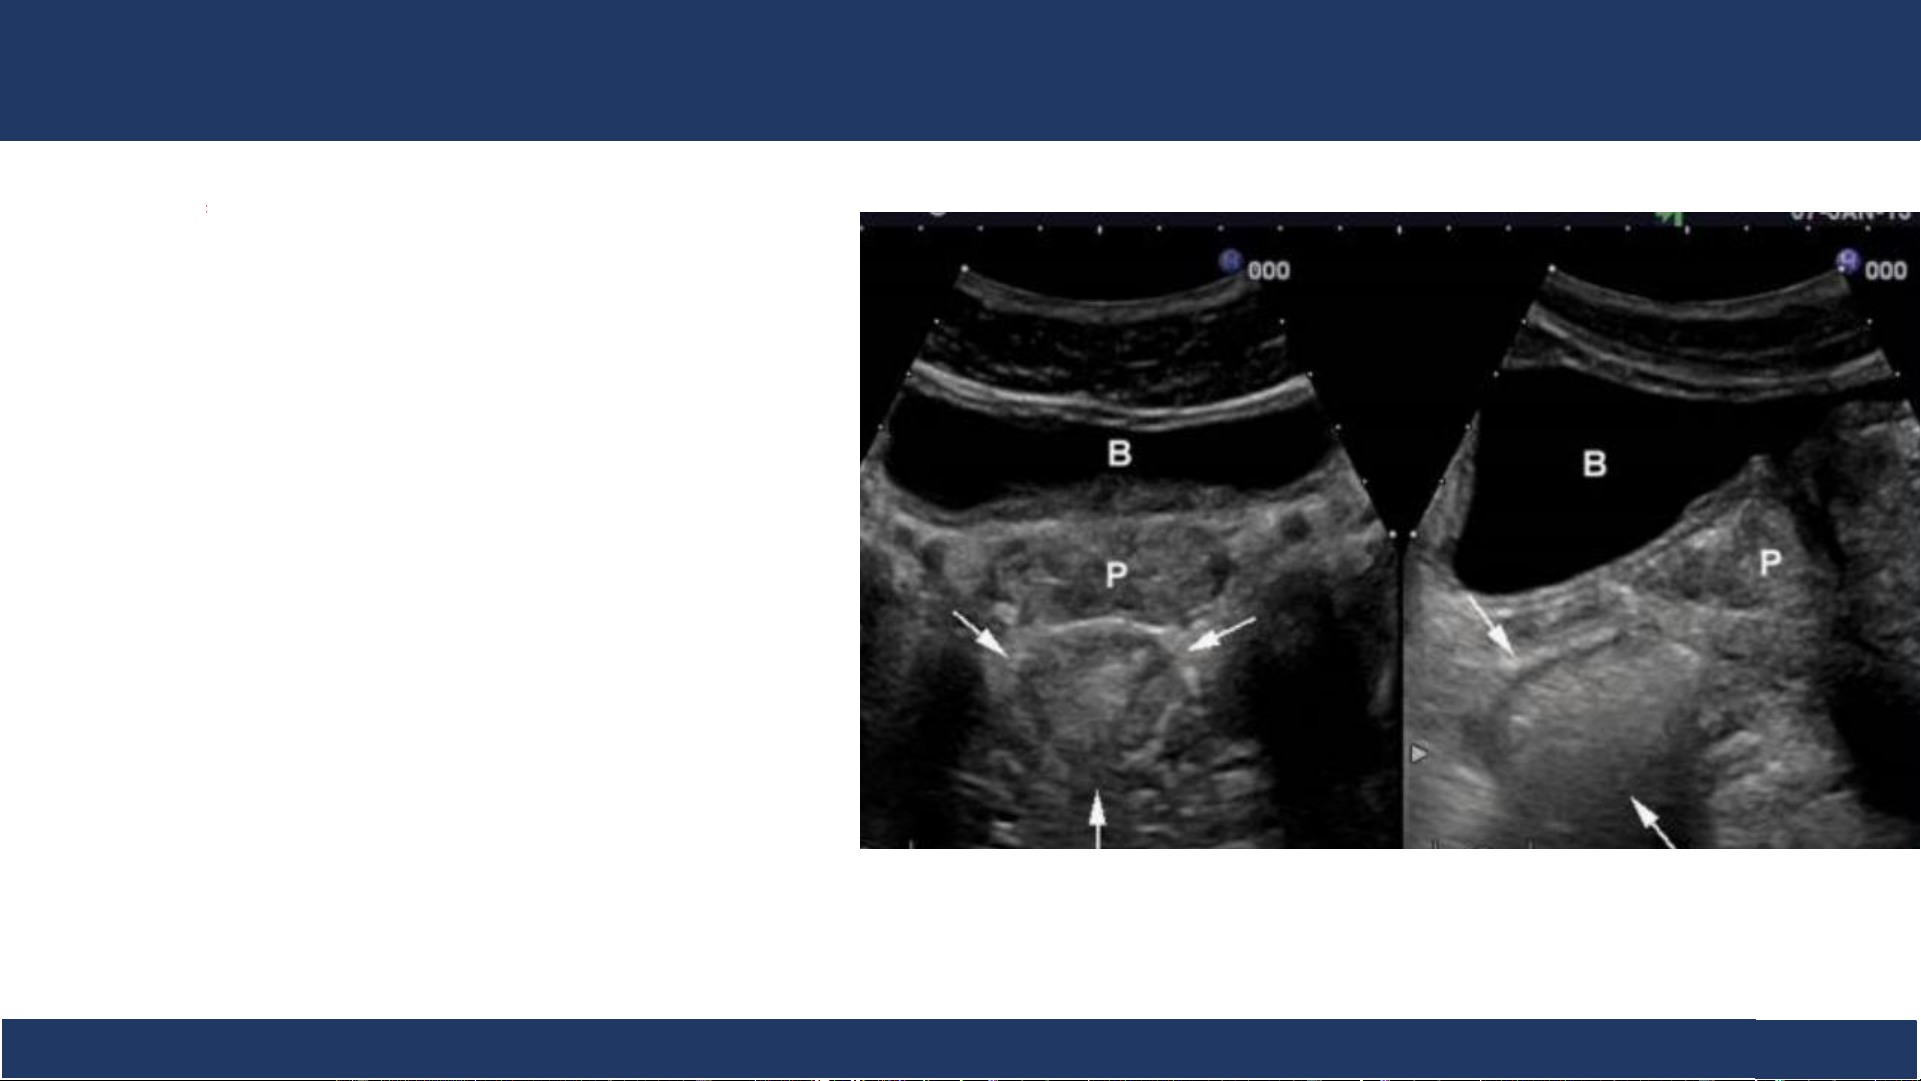

hình ảnh, ĐHYD TPHCM 19 SA: trực tràng

- Trực tràng: nằm phía sau .

bàng quang và tiền liệt tuyến. - Lòng chứa hơi. Bệnh v B iệ ộ môn n Nh Chẩ i Đồng n đoán 1